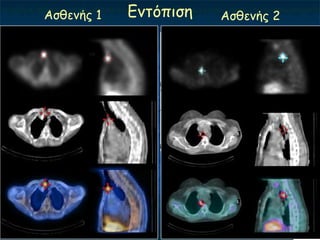

Αζζεκήξ 1   Γκηόπηζε   Αζζεκήξ 2

Αζζεκήξ 1 Γκηόπηζε Αζζεκήξ 2 ΢θαγή

Αζζελής κε κεγάιοκε ιεηηοσργηθό όδο ΑΡ ιοβού Αδέλφκα θαη σπερπαραζσρεοεηδηζκό Θσρ. όδος παραζσρεοεηδώλ Πνςσμε ιήρε Πρόζιευε 99mTc- Αδέλφκα παραζσρεοεηδώλ πίζφ από όδο ζσρεοεηδούς όδο Sestamibi από ηολ 2 ώνεξ

Οπηζζο-ηρατεηαθό αδέλφκα ΓΝΣΟΠΙ΢Η Ονζόημπμ Mibi early Mibi late αδέκςμα; Pertechnetate Αθαίνεζε

Οπηζζο-οηζοθαγηθό αδέλφκα Πνώσμε 2 ώνεξ Φοπνόξ ζονεμεηδηθόξ όδμξ Όδμξ Αδέκςμα Tc-99m Αθαίνεζε